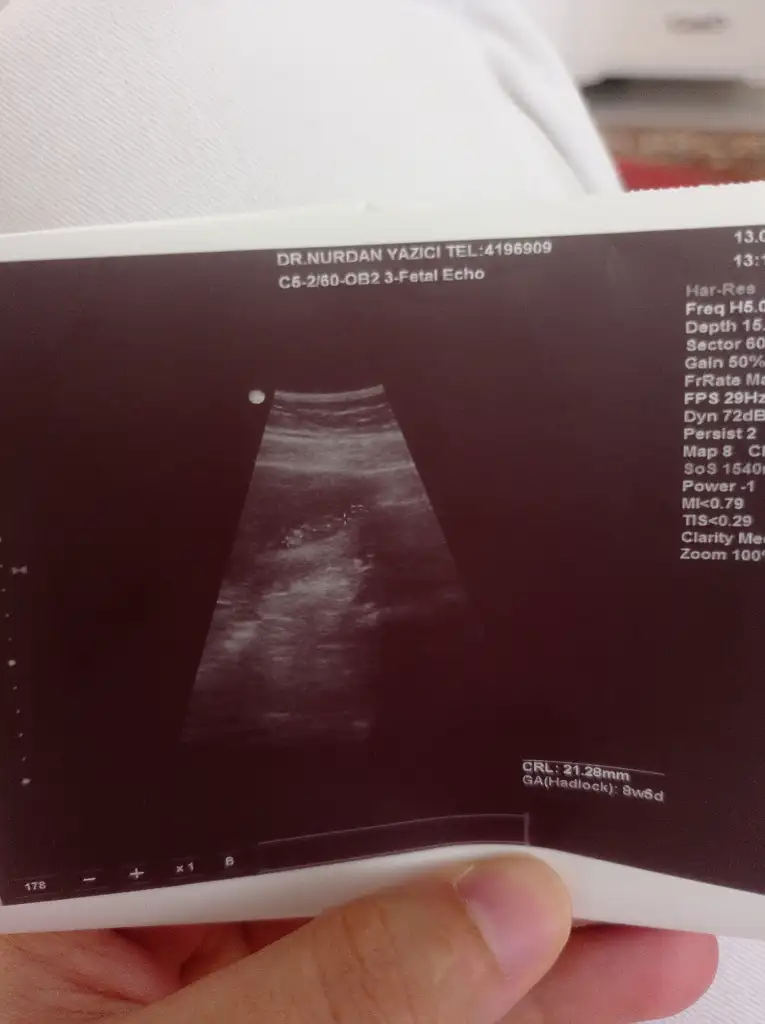

Erkek sanırım doktor bir şey demedi miArkadaşlar benimde ultrason goruntume bakar mısınız 13+4 haftalık cinsiyeti nedir sizce

Doktor ilk erkek gibi sanki dedi ama sonrasında net değil dedi çıkıntı var ama erkek mi kız mı belli değil dedi. 3 hafta sonra artıkErkek sanırım doktor bir şey demedi mi

Kizlar siz anliyorsunuz galiba benimkine de bakar misiniz karindan ultrason

Erkek8+3 karından ultrasonla çekildi cinsiyet tahmini var mı

Kesenin üst tarafındaysa erkek diyorlar sizin de erkek buna göreKizlar siz anliyorsunuz galiba benimkine de bakar misiniz karindan ultrason